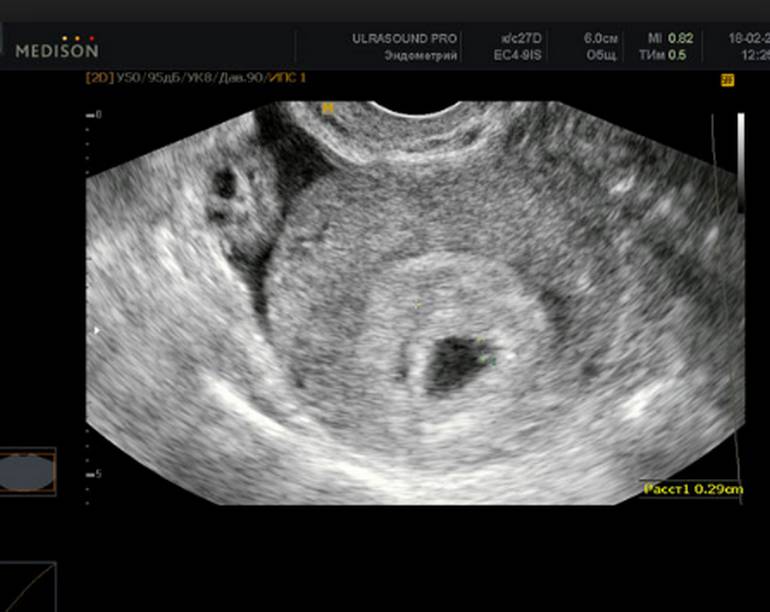

Маточная беременность раннего срока, плодное яйцо

На 4 неделе может быть видно плодное яйцо, но эмбрион еще не всегда визуализируется.

На каком сроке можно увидеть плодное яйцо на УЗИ

Информативность узи на ранних сроках беременности